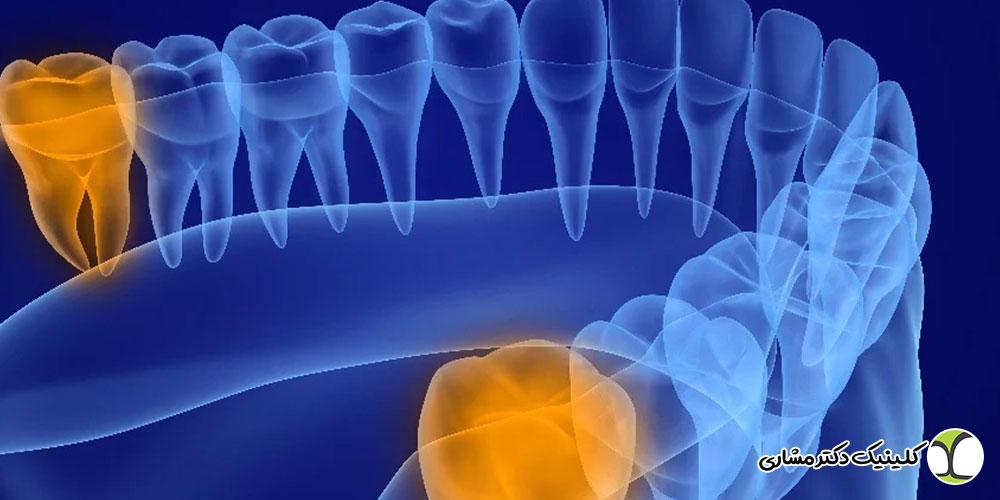

دندان عقل، یا همان دندان آسیا سوم، آخرین دندانی است که در دهان انسان رشد میکند؛ معمولاً در سنین جوانی یا بلوغ. موقعیت مکانی این دندان در انتهای قوس فکی، همراه با زمان دیرهنگام رویش، باعث میشود که دندان عقل اغلب با چالشهای خاصی مواجه شود. در بسیاری از موارد، به دلیل فضای کم یا رشد نامناسب، دندانپزشکان تصمیم به کشیدن آن میگیرند. اما در شرایطی که دندان عقل به شکل صحیح رشد کرده و به حفظ آن نیاز باشد، و این دندان دچار پوسیدگی عمیق یا عفونت شود، بحث درمان ریشه (عصبکشی) دندان عقل مطرح میشود.

- رشد نامناسب: دندان عقل ممکن است به صورت نیمهنهفته (بخشی از آن زیر لثه مانده) یا کاملاً نهفته (داخل استخوان فک) رشد کند، که این شرایط معمولاً عصبکشی را غیرممکن یا بیفایده میسازد.